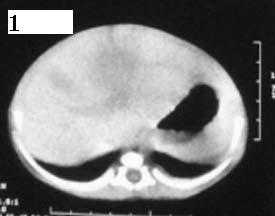

这个病例定位诊断:1、可以肯定肿块不在肝脏。2、肿块在腹膜后,因为肠管向前侧方推移,肾脏明显向后推挤,腹主动脉及下腔静脉被肿块包绕。

定性诊断比较困难,该病例肿块为实质性,小儿最常见的腹膜后肿瘤第一位应该是-----神经母细胞瘤!

我的意见是-----定位诊断是“1、可以肯定肿块不在肝脏。2、肿块在腹膜后,因为肠管向前侧方推移,肾脏明显向后推挤,腹主动脉及下腔静脉被肿块包绕。”

肝脏只是受推压改变,支持神经母细胞瘤

右中下腹部囊实性密度影,内有小细条状钙化影,胃及腹部肠管受压向左移位,肾脏受压向后移位,腹主动脉及下腔静脉包饶。考虑腹膜后畸胎瘤可能性大。